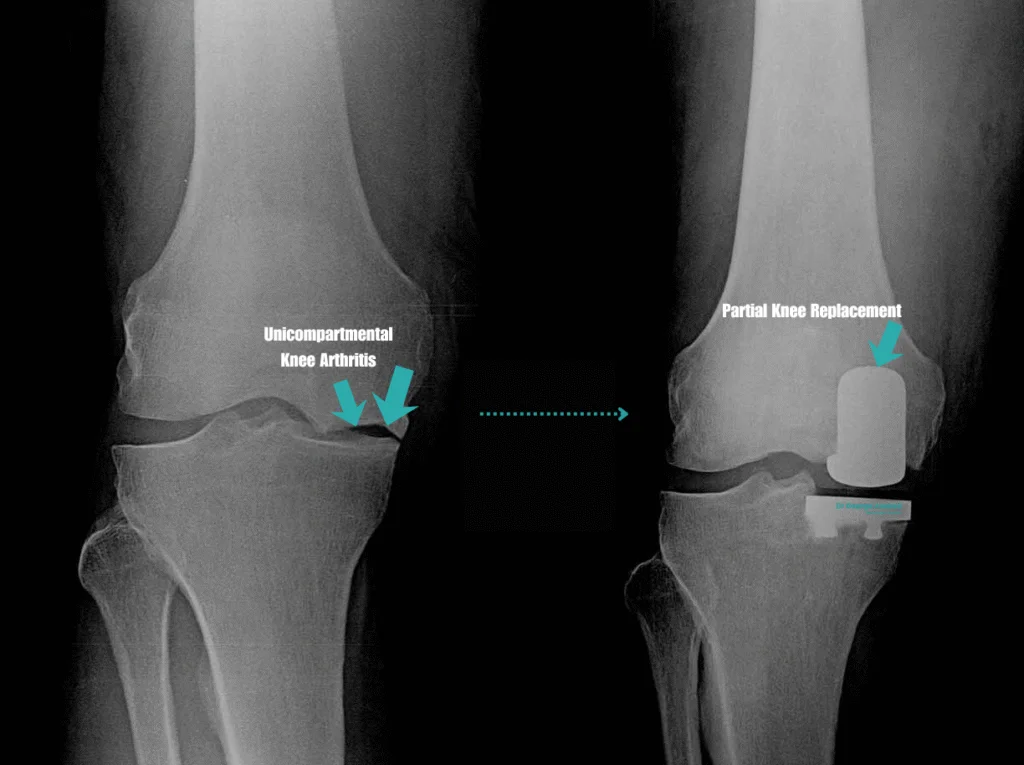

Partial knee replacement surgery, also known as unicompartmental knee arthroplasty, is a surgical procedure used to treat arthritis that affects only one part of the knee joint. Unlike total knee replacement, which replaces the entire joint surface, a partial knee replacement involves resurfacing only the damaged compartment, typically the medial (inner), lateral (outer), or patellofemoral (kneecap) region, while preserving healthy bone, cartilage, and ligaments.

A partial knee replacement, also known as unicompartmental or, hemi knee arthroplasty, is a surgical procedure used to treat arthritis or damage that is limited to a single compartment of the knee joint. Unlike a total knee replacement, which replaces all the surfaces of the knee, a partial knee replacement targets only the affected area, either the medial (inner), lateral (outer), or patellofemoral (kneecap) compartment.

How is partial knee arthritis different from total knee arthritis?

Knee arthritis does not always affect the entire joint. In many patients, the wear and tear is isolated to a specific region, or “compartment,” of the knee. Understanding the difference between partial and total knee arthritis can help clarify whether a partial knee replacement may be a suitable surgical option.

Partial knee arthritis (unicompartmental disease)

Partial knee arthritis occurs when the degenerative changes are limited to just one of the three main compartments of the knee:

In these cases, the other compartments of the knee remain healthy, and the supporting ligaments such as the ACL and PCL are still functioning. Patients with partial knee arthritis often experience pain, stiffness, or swelling that is localised to one side of the knee or behind the kneecap, rather than throughout the entire joint.

Total knee arthritis (tricompartmental disease)

Total knee arthritis, or tricompartmental osteoarthritis, involves degenerative changes across all three compartments of the knee. This more widespread damage often results in:

Patients with this level of joint degeneration are more likely to require a total knee replacement, which involves resurfacing the entire joint with prosthetic components.

Why this distinction matters

The type and distribution of arthritis in your knee is a major factor in determining which treatment is most appropriate. If arthritis is isolated and the rest of the knee is well-preserved, partial knee replacement may be considered. This allows preservation of natural structures and may offer a quicker recovery and more natural knee feel after surgery.